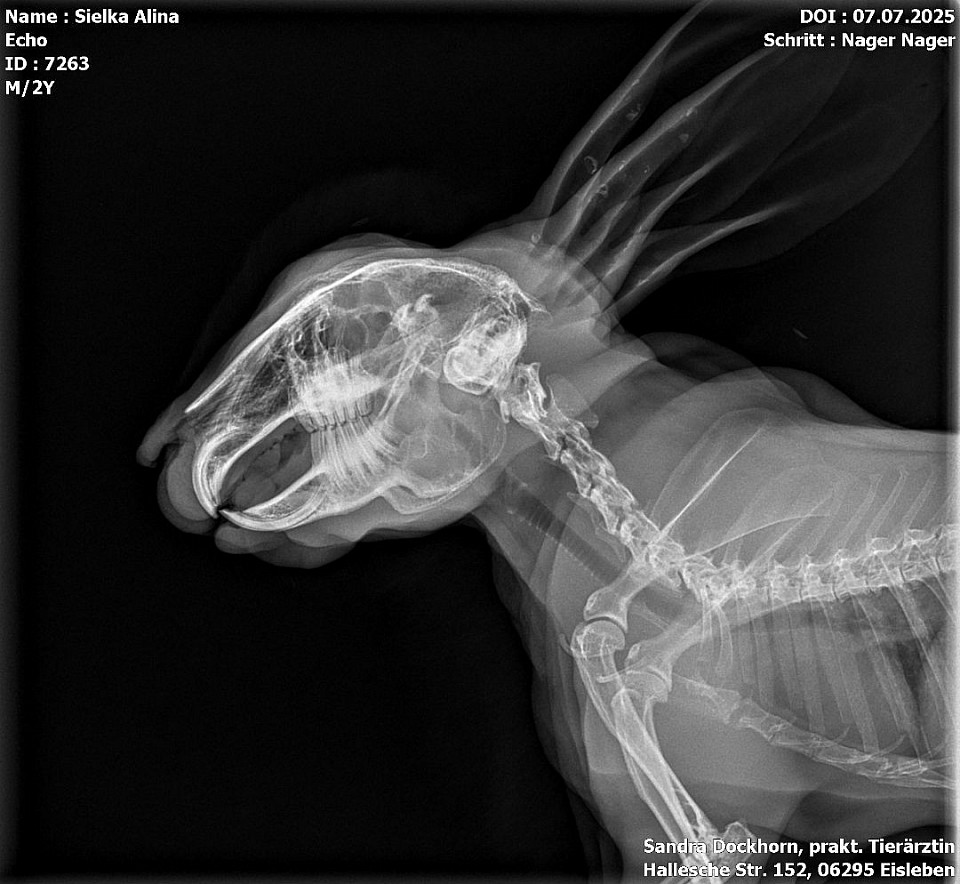

Röntgenbilder

Interressant, oder? Troll sein gebrochener Zeh und Echo seine Kniefraktionen und sein Stufengebiss.

Echo bekommt ein vorbeugenes Mittel gegen Arthrose und kriegt einen Zahnarztbesuch (Leipzig) und Troll wird jetzt bei Dr. Rust im Salzatal vorgestellt.